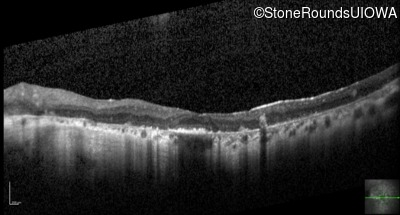

Optical Coherence Tomography - Left - 20/70

Exemplar / OCT Stack